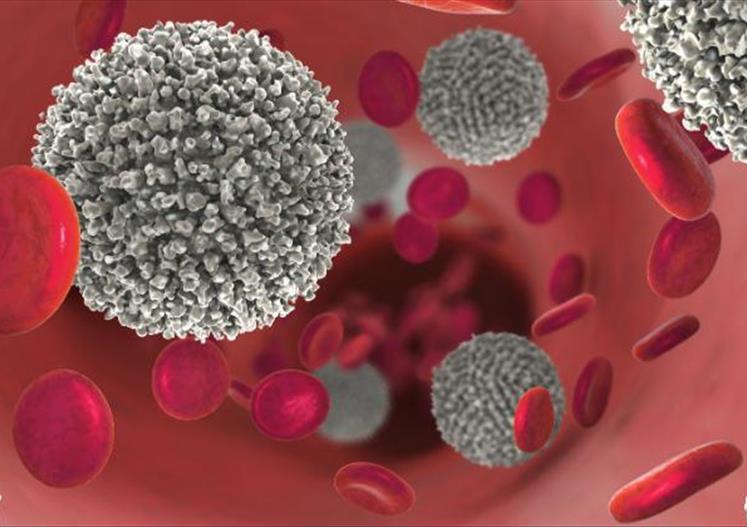

En el marco del Día Mundial de la Lucha contra el Cáncer, que se conmemora cada 4...

En el campo de la hematología, la investigación científica ha impulsado en los últimos años una transformación...

El Dr. Claudio Martín, Presidente de la Asociación Argentina de Oncología Clínica, ofrecerá una masterclass exclusiva dirigida...